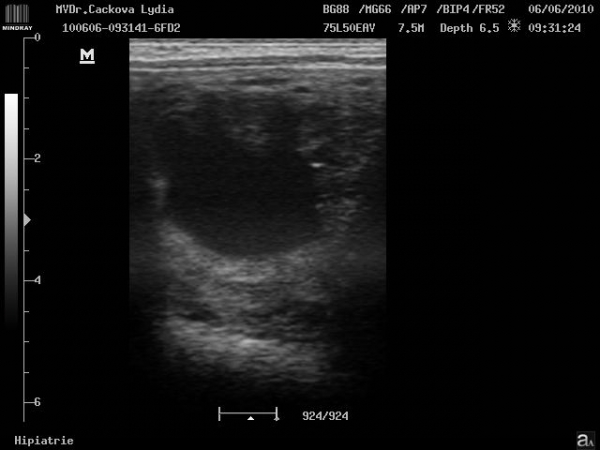

ultrasonografické vyšetření klisny